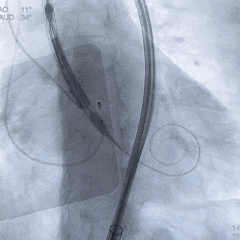

脱钩后造影,瓣膜位置可,几乎无瓣周漏

左冠切线造影,确认冠脉无遮挡

外周血管造影无损伤,手术结束